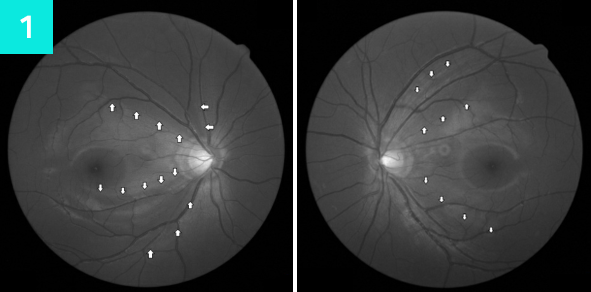

녹내장이 진행될수록 시신경 유두테의 손실이 증가하여 시야가 점점 줄어듭니다.

정밀한 단층 촬영이 가능한 안과 CT 검사를 통해 녹내장의 초기 징후를 발견할 수 있습니다.